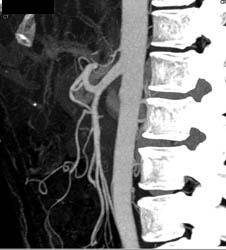

Common Trunk to Superior Mesenteric Artery (SMA) and Celiac Artery